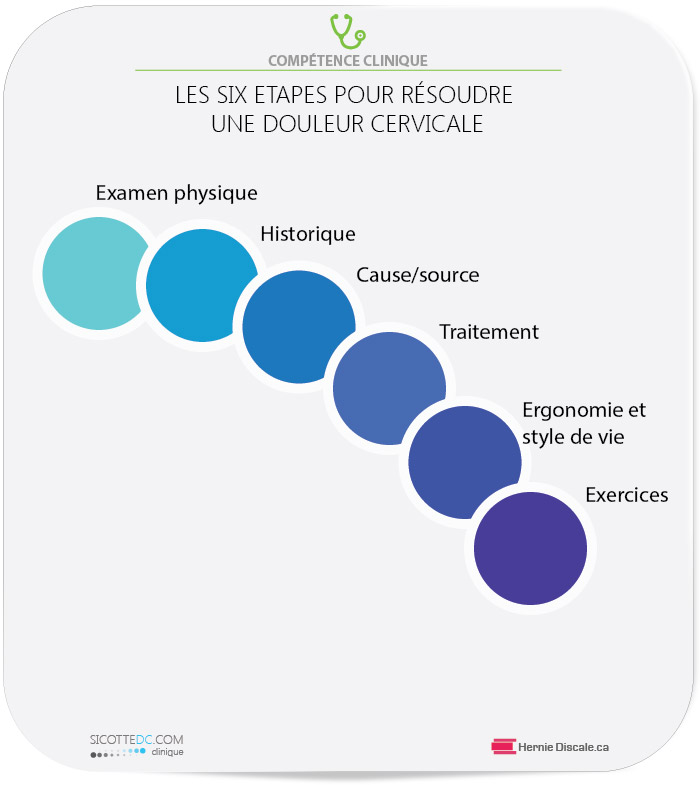

SIX ÉTAPES D’EXAMEN PHYSIQUE POUR LA DOULEUR CERVICALE

Historique : La suggestion d’un diagnostic spécifique est obtenue en révisant avec le patient les facteurs attenants et aggravants.

Examen : Un examen physique est nécessaire afin de déterminer l’ampleur de la situation. Certaines personnes peuvent avoir des douleurs qui irradient jusqu’aux doigts. Plusieurs régions vertébrales peuvent être en cause (région costotransverse).

Cause : Les causes sont multiples. De nombreux patients passent de longues heures à l’ordinateur en position statique.

Traitement : Les soins seront des manipulations et des flexions-distractions Cox®appliquées à la région cervico-dorsale.

Ergonomie : Le poste de travail doit être modifié. Les habitudes de vie doivent changer. Lire au lit avec de multiples oreillers est fortement déconseillé.

Exercices : Un régime quotidien d’exercices à la maison est prescrit, ce qui est très utile pour maintenir les acquis des soins prodigués en clinique.